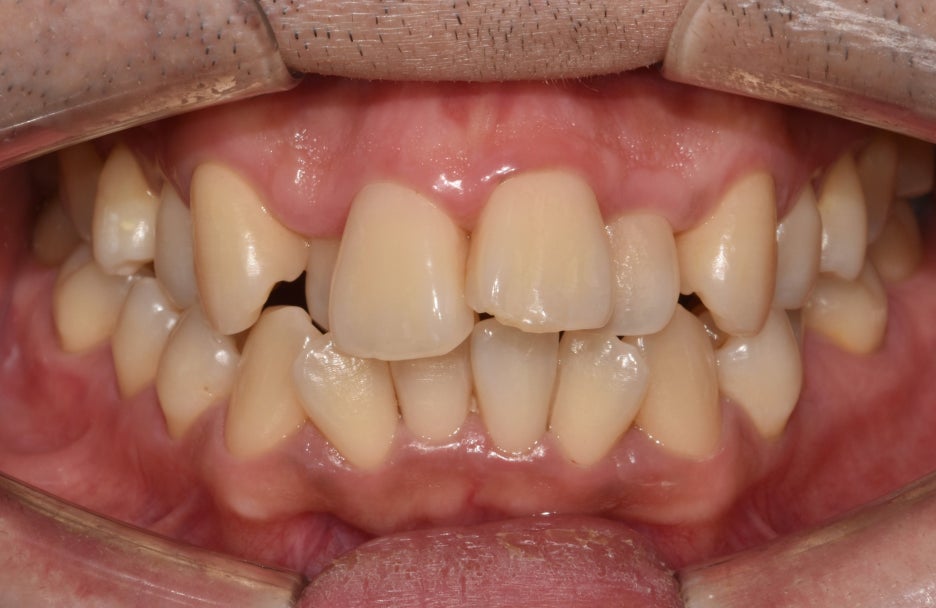

실제로 이렇게 앞니 뻐드렁니와 총생 등

갖가지 문제를 가지고 있는 분들께서는

평소 구강 관리가 어렵습니다.

제대로 칫솔질이 되지 않으니

치석도 자주 쌓여 잇몸에 염증 발병률도 높아집니다.

좀 더 자세히 내부를 들여다봤을 때,

되게 어지럽게 배열되어있는 모습을 볼 수 있습니다.

특히나 전치부에 집중된 총생(crowding)은

배열을 들쑥날쑥하게 만듭니다.

사진에서 보여지듯이 12번은

반대교합의 형태도 나타내고 있었는데요.

다른 곳들은 윗니가 아랫니를 덮는 반면에

오른쪽 아랫니 송곳니 부분이 위쪽의 12번을

덮고 있는 형태로 반대교합을 보여줍니다.